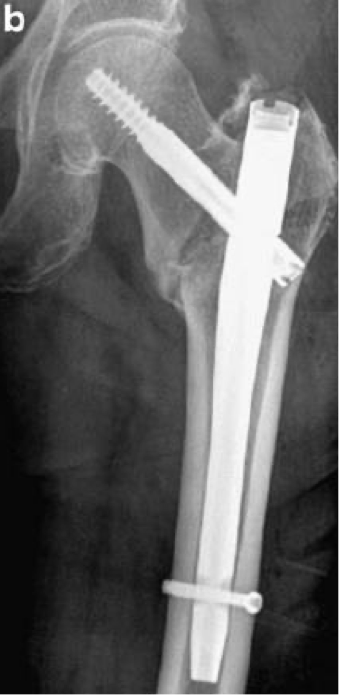

when do you use a dynamic hip screw?

-intertrochanteric fractures

what is an intramedullary hip screw?

-a longitudinal rod in the medullary canal of the femur

-aka IM nail

<p>-a longitudinal rod in the medullary canal of the femur </p><p>-aka IM nail</p>

when do you use an intramedullary hip screw

-long bone diaphyseal fractures

-may be combine with dynamic screw for intertrochanteric fractures